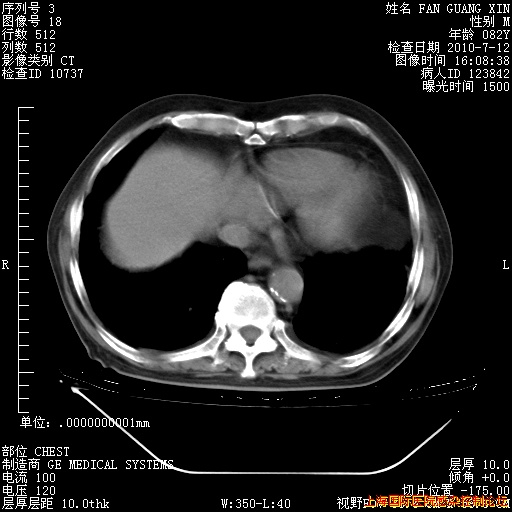

6月12日纵膈窗